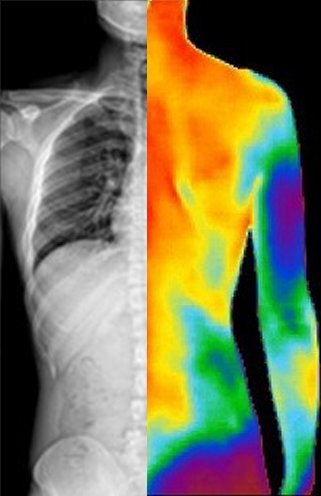

The physiological effects of dysautonomia include erroneous management of the capillary beds that allow for the dissipation of heat from the core of the body. The parasympathetic fibers that affect and give input to these beds are direct from their centers in the cervical and lumbopelvic portions of the spinal cord. The sympathetic fibers originate in the thoracic segments of the spinal cord and enter into the prolific sympathetic chain ganglia.

When there is an imbalance or interference in the functioning of these centers and their control messages, the heat dissipated will immediately be changed depending on the severity and impact of that interference and imbalance.

The Titron Thermography Scanners read the temperature bilaterally simultaneously to gather the data on the paraspinal temperature radiated from these capillary beds. The graphs produced by the scan show the temperature of the scanned anatomy, and with some math, show the balance of the temperatures graphed at that time. Coupled and layered with other graphs from other days and before- and after-visit scans, if patterns of non-adaptation appear, it would indicate an abnormal control system and possible dysautonomia.